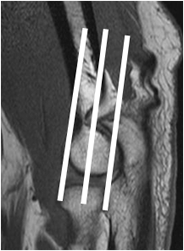

La RM debe incluir cortes axiales, sagitales y coronales. Tener en cuenta que los cortes coronales, deben realizarse con una angulación posterior de 20º en relación con el eje del húmero, lo que permite la mejor visualización de los ligamentos. (1). (Fig 6).

Fig 6. Orientación de cortes coronales en RM.